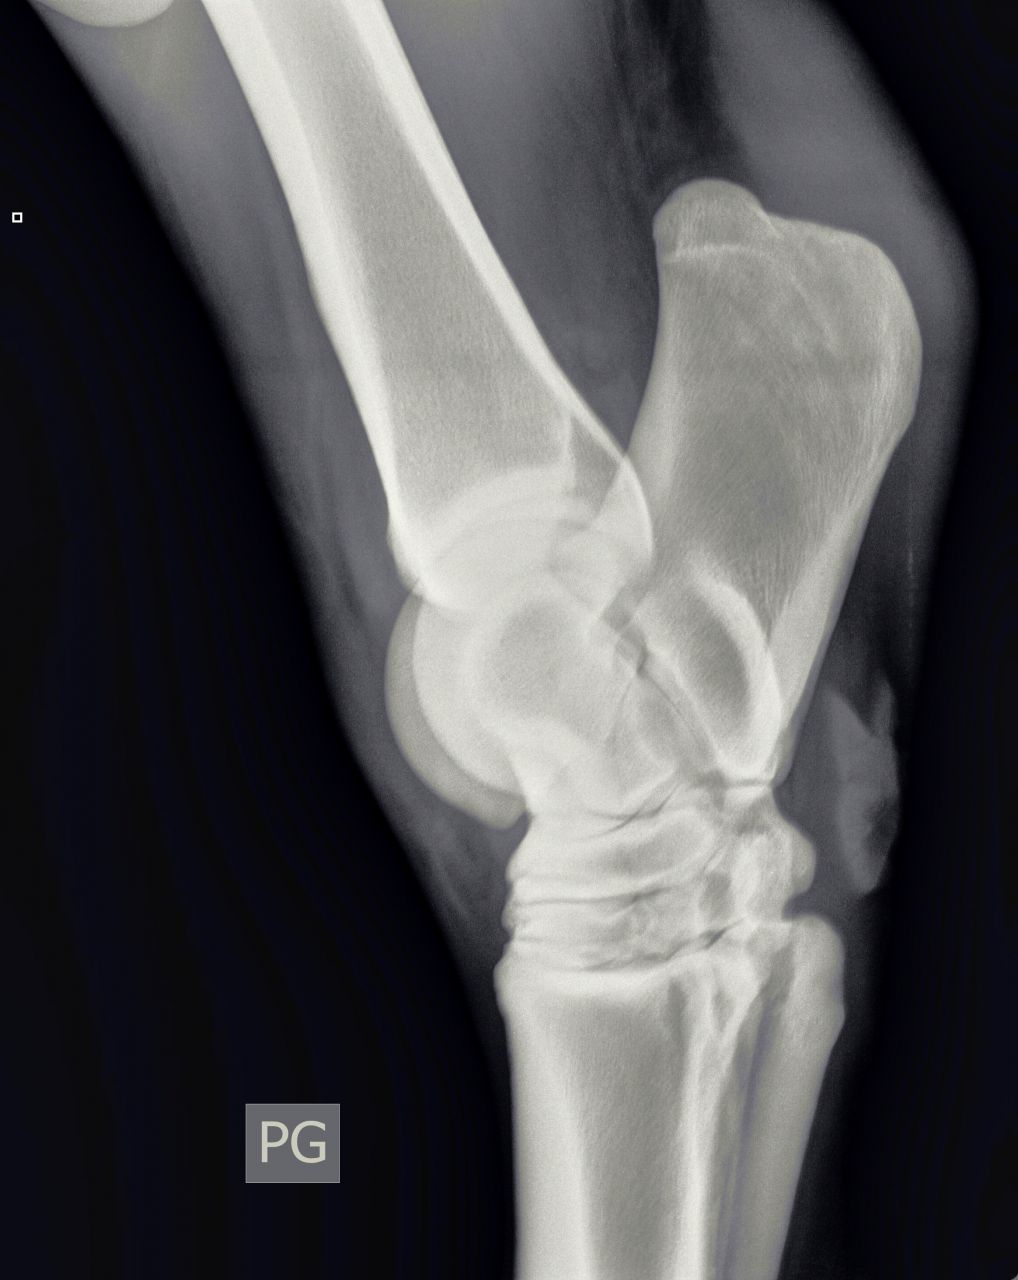

| Dire merci | Bonjour, le vétérinaire vient de diagnostiquer un début d'éparvin sur un des postérieurs de ma jument. Voici les radios : [url=https://www.1cheval.com/membre/services/photos/images/198166.jpg" class='zoombox zgallery3311504' ] ![]() [/url] [url=https://www.1cheval.com/membre/services/photos/images/198165.jpg" class='zoombox zgallery3311504' ] ![]() [/url] [url=https://www.1cheval.com/membre/services/photos/images/198164.jpg" class='zoombox zgallery3311504' ] ![]() [/url] il me propose comme soins : tildren en IV et ferrure avec plus d'éponge Que pensez-vous de ce traitement? je suis perdu quant à la marche à suivre (le traitement vaut 500€ et sans garanti de résultat même si le véto a bon espoir) Ceci dit, je viens de rencontré quelqu'un à qui ce même véto à déconseillé le tildren pour sa jument qui a un éparvin. Une amie en a parlé à son véto (spé équin aussi) qui lui a dit qu'on pouvait tenter aussi les ondes de choc. Je ne connais pas le prix Quelqu'un a-t-il déjà testé sur l'éparvin? Que faire d'autre? J'ai bien fait cure d'harpagophyt, sans amélioration. en voici plus sur ma jument : Celle-ci est une arabo-appalossa de 12 ans, née chez moi, débourrée à 5-6 ans et qui fait du loisir modéré. Elle s'est mise à boiter suite à une endurance (10 km) où il y avait un fort dénivelé en tout début et toute fin de (au point que je suis descendu d'elle pour descendre le chemin en crabe). La jument était largement entrainée avant (elle aurait pu courir une 20 voir une 40) elle est au repos depuis (ca fait 3 mois et demi) et j'ai l'impression que la boiterie s'aggrave un peu (c'est intermittent) lorsque je l'ai emmener au vétérinaire, elle ne boitait pas, les tests de flexions ont ré-déclenché la boiterie. La jument est ferrée en rolls des 4 pieds depuis 6 mois (et plus d'un an des antérieurs) |